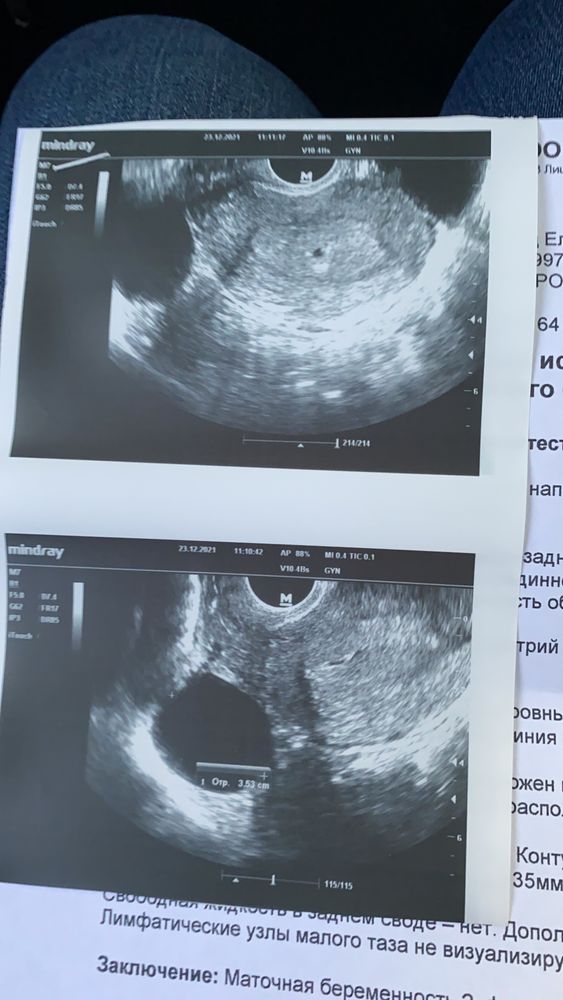

Здравствуйте,это может быть киста жёлтого тела,по месячным у вас срок 4 или пять недель,если была поздняя овуляция тогда меньше,сходите на УЗИ через пару недель,сдайте ХГЧ в динамике. Мне в 6-7 недель говорили срок 2-3 и тоже киста 4 см и подозрение замершей,сходила на следующий день к другому узисту 6-7 недель и сердечко. Сейчас лежит в кроватке моя 3б,пять месяцев исполнилось

У вас все хорошо. Развивающаяся маточная беременность и хорошо видное ПЯ.

Lychek, была сегодня у врача. 5 недель нам. Маточная. Все хорошо

Елена, ну что, нам оказывается 5 неделек только и все хорошо Изображение